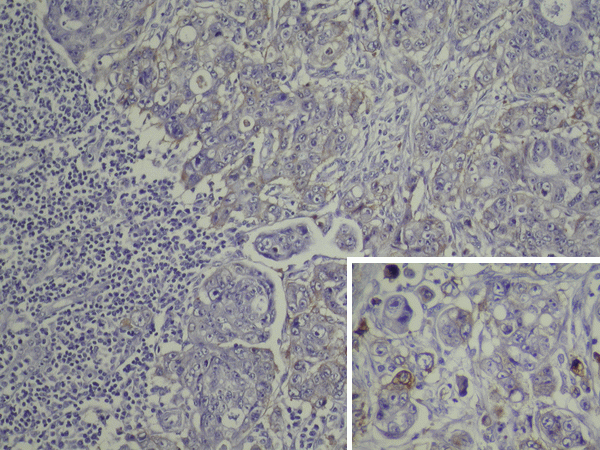

En 46 casos analizados, la expresión del Factor de Crecimiento Epidérmico en el tumor primitivo (EGFR-p) fue positivo en 22 (47.8%) y negativo en 24 (52.2%); en los 4 pacientes restantes, no obtuvimos muestra del tumor primitivo (Figura 1).

Figura 1. Pared de intestino grueso infiltrada por un adenocarcinoma moderadamente diferenciado.

EGFR positivo en las células tumorales (EGFR-p). Recuadro: detalle